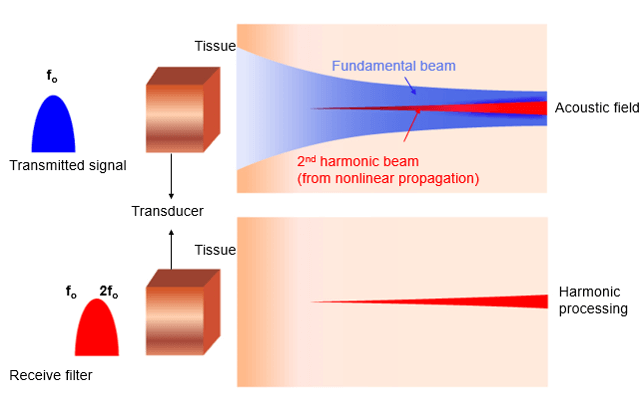

Non-Linear Propagation

Linear and nonlinear propagation are terms used to describe how soft tissues respond as the ultrasound wave propagates.

When the acoustic pressure of the ultrasound wave in soft tissue is small, the tissue behaves in a linear fashion, which means that the tissue expansion (rarefaction) and compression propagate at the same speed.

Nonlinear propagation occurs when high-pressure ultrasound waves travel through a compressible medium and the transmitted ultrasound pulse makes less compression than rarefaction.

- Propagation speed increases with density (pressure)

- The wave moves faster when the pressure is higher (peaks) and slower where it is lower (troughts)

- Any change from a perfect sinusoid creates harmonics

- The higher the amplitude, the more the effect

Principle

Harmonic frequencies are integer multiples of the fundamental frequency (for example if the fundamental frequency is f0, the harmonics have frequencies of 2f0, 3f0, and so on). The amplitudes of the harmonic waves are almost always lower than those of the fundamental frequency waves.

As we mentioned previously, the transmitted pulse consists of a range of frequencies centered around f0. In a linear medium, the echo pulse frequency is the same as the fundamental frequency but has lower energy, whereas the nonlinear medium results in harmonic waves of higher frequency and lower energy as shown in this figure. It is important to note that the majority of clinical US systems use second harmonic (ie, 2f0) echoes for THI image formation.

Now, let’s go deeper and explain the fundamental wave elimination techniques. The fundamental and the second harmonic frequencies are received together in the time domain as a combined distorted wave. High-quality THI primarily depends on the achievement of the complete elimination of the echoes at the fundamental frequency. Various techniques are used to remove the fundamental wave in THI, including bandwidth receive filtering, pulse inversion, side-by-side phase cancellation, and pulse-coded harmonics.

Bandwidth receive filtering is a signal processing technique in which lower frequencies that are more likely to have emerged from the fundamental beam are filtered out, and higher-frequency harmonic echoes are used to generate the image. In this technique, noise such as reverberation artifact and tissue aberrations diminishes and enhancement is improved.